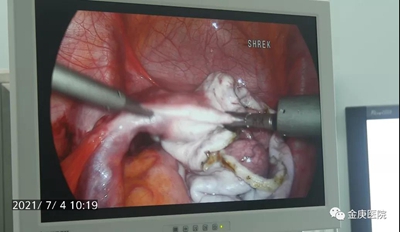

這次腹腔鏡手術(shù),由豐富臨床經(jīng)驗的外二科主任焦建中主刀,結(jié)合影像資料,精準(zhǔn)定位,采用引流方式,從包塊中引出近3000毫升的清色液體, 40多分鐘手術(shù)順利結(jié)束,從住院到出院共7天,出院時患者就能自主下地行走。

據(jù)外二科主任焦建中介紹:金庚醫(yī)院采作中醫(yī)藥與腹腔鏡手術(shù)相配合,引領(lǐng)中醫(yī)創(chuàng)新發(fā)展,腹腔鏡膽囊、膽總管切開取石術(shù)、疝氣修補術(shù)、甲狀腺術(shù),取得了顯著的康復(fù)效果,相比常規(guī)腹腔鏡手術(shù),術(shù)中并發(fā)癥少、患者療程短、費用低。